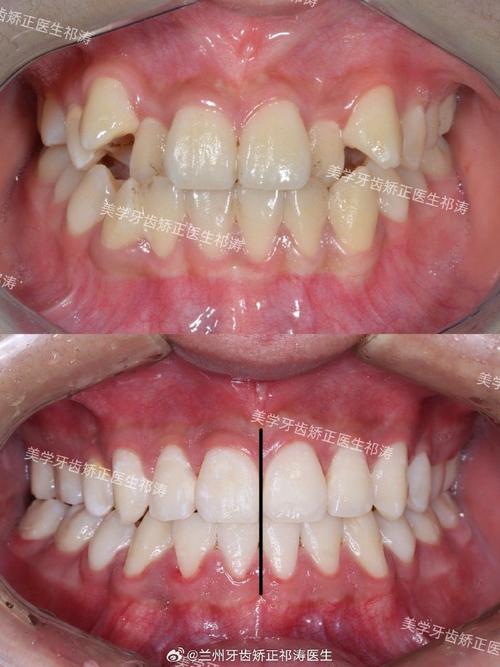

- 最常用且有效的解决方案。 如果拥挤的主要原因是缺牙后邻牙倾斜、对颌牙伸长、或其他牙齿移位导致的排列不齐,正畸治疗是首选。

- 目的: 将倾斜的邻牙扶正,将伸长的对颌牙压低(可能需要配合牙冠或嵌体降低高度),将移位的牙齿排列整齐,建立稳定、协调的咬合关系。

- 方式: 可以选择传统固定矫治器(钢牙套)、陶瓷矫治器、隐形矫治器(如隐适美、时代天使)等,矫正方案需要考虑种植牙的存在,设计时可能需要特殊处理(如种植体支抗)。